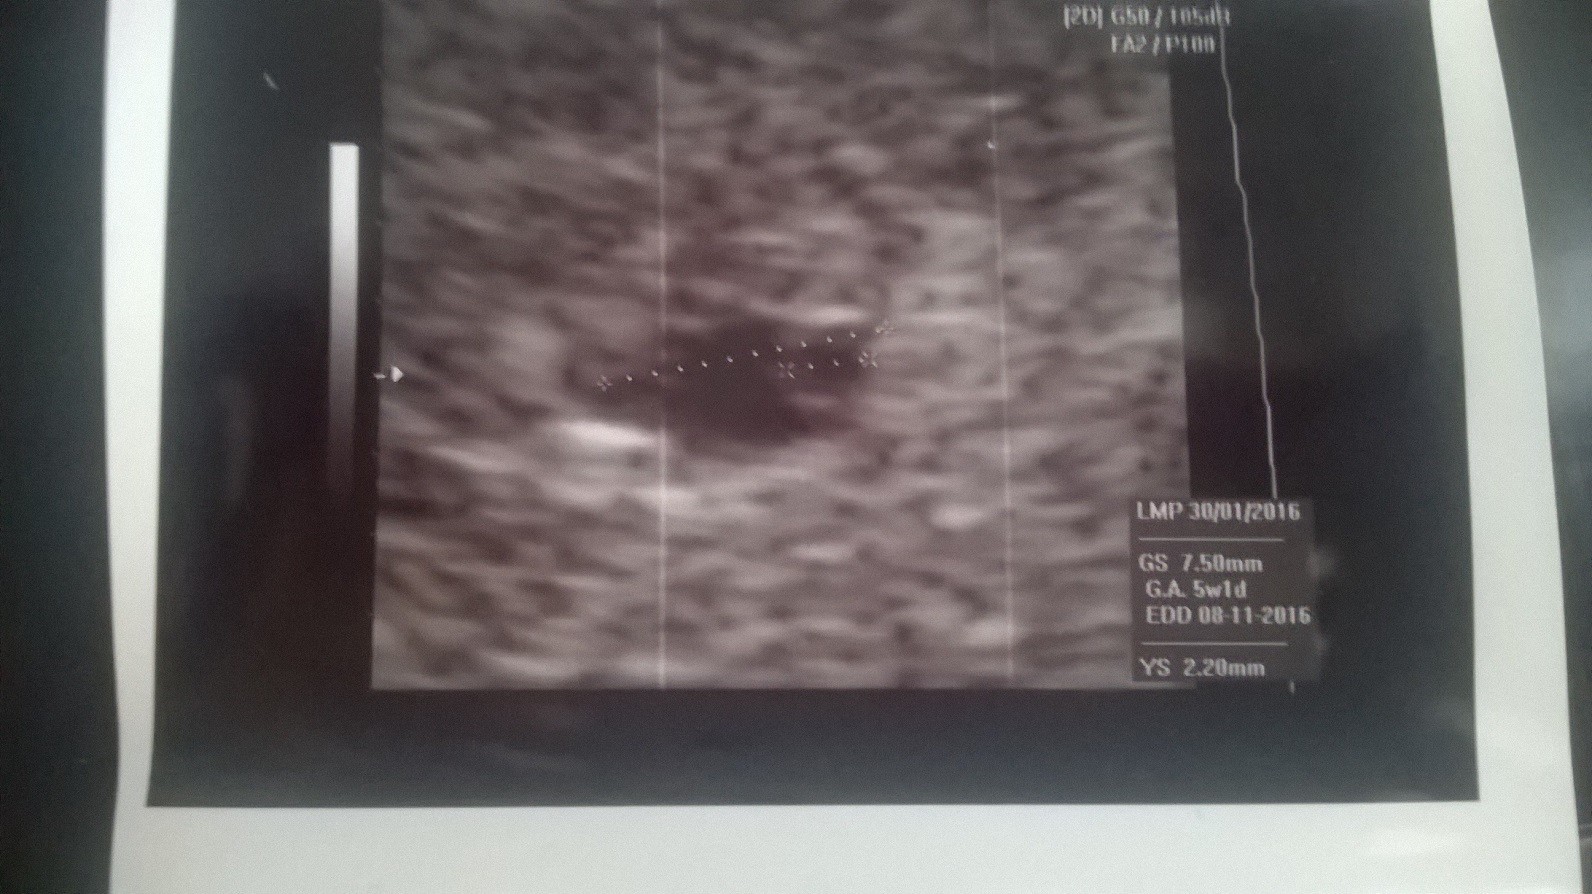

Patrząc na pomiary to faktycznie wydaje się, że coś jest nie tak, ale zobacz jak kiepski jest obraz na tych pierwszych dwóch. Tam milimetr w tą czy w drugą już robi różnicę. A co do wymiarów to nie brałabym pod uwagę tych robionych przez twoją byłą gin, bo po prostu się nie przykładała. Tak na prawdę po prostu trzeba czekać na rozwój sytuacji i wierzyć, że będzie dobrze.